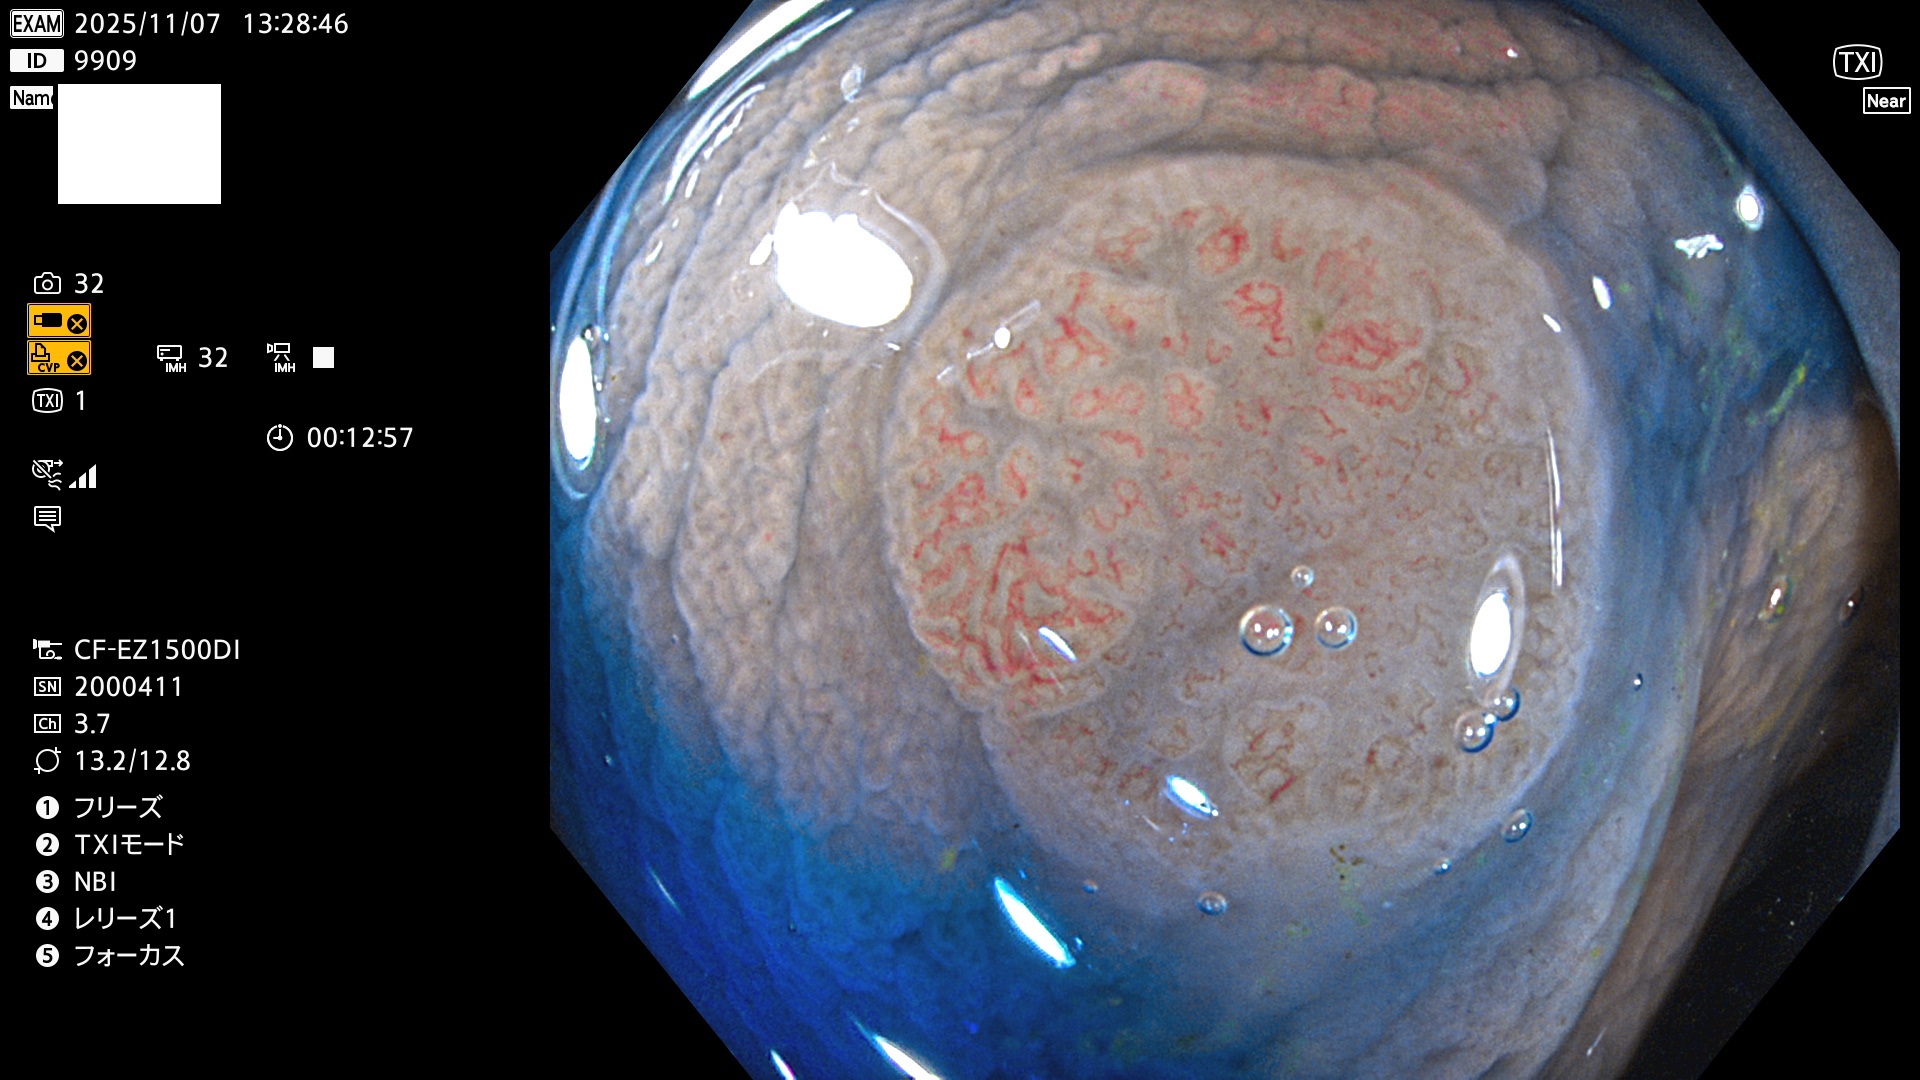

完全に平坦な物をUb、陥凹している物をUcと呼びます。Ubは認識が困難で、Ucはびらん(炎症)と紛らわしいために見落とされやすく、「内視鏡後・大腸癌」の原因になります。

専門的)Uc=De Novo癌? 内視鏡の解像度が低かった時代、このような説もありました。しかし今日の高精度内視鏡では良性の微小なUc型腺腫(APC遺伝子異常の腺腫)が日常的に見つかります。Ucこそが多段階発癌(Adenoma-Carcinoma Sequence)のMain Routeです。

2025年11月6日〜11月9日の4日間(40件)6個 (Uc_ADR=6個/40人=15%)